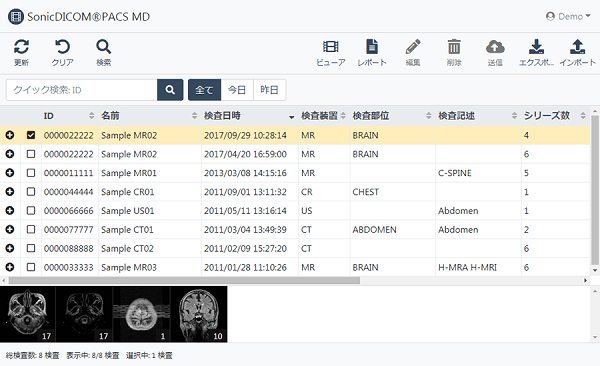

本製品は、CRやCT、MRIなどの検査装置から発生するデジタルな医用画像データを保管、管理し、それらの画像をWebブラウザで参照することができるソフトウェアです。2018年の販売開始以来、Webブラウザベースの高速画像ビューアを搭載し、リーズナブルなコストで導入できることから、高い評価を得ています。